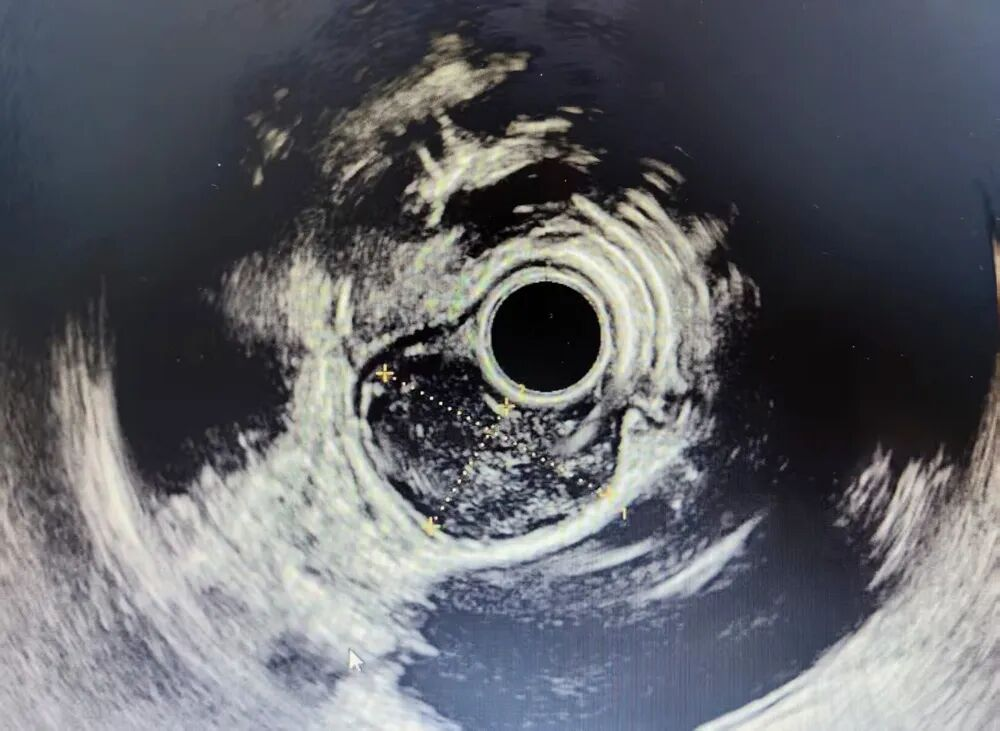

患者为40岁男性,因体检完善胸部CT发现食管胸中上段见团片状等密度影,相应食管管腔狭窄,大小约5.9cmx2.6cmx2.0cm,考虑平滑肌瘤可能。经超声内镜进一步检查考虑该肿物为来源于食管固有肌层浅层的平滑肌瘤。传统外科手术需开胸或胸腔镜下切除,创伤大、恢复慢。为充分做好术前评估及术中、术后的风险评估,消化内科组织了多学科联合会诊(MDT)。讨论会上,放射科刘向华副主任团队及内镜中心刘烈辉主任团队再次详细阅读患者的CT图片及内镜图片,对患者肿物层次及毗邻脏器做了精准评估。胸心外科和乳腺外科张广云主任团队会后充分向患者解释了外科手术与STER手术的优缺点,并表示将全程提供外科后备力量支持。经过与患者充分沟通后,决定采用更为微创的STER技术。

▲患者术前超声内镜检查图像